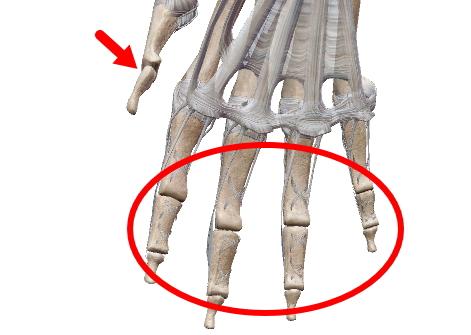

| 球関節の楕円バージョン。楕円なので回旋は出来ない2軸の関節。環椎後頭関節、橈骨手根関節、中手指節関節(母指以外)。 |

| 馬の鞍(くら)を上下に重ねたような形から鞍関節(あんかんせつ)。楕円関節同様回旋は出来ない2軸の関節。母指の手根中指節関節。 |